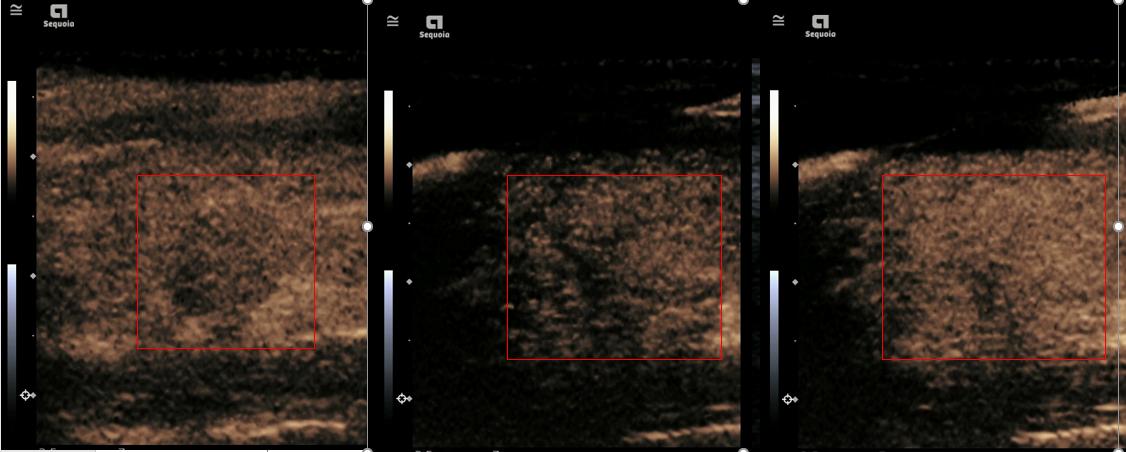

甲状腺肿瘤造影图像显示       据悉,超声造影技术为超声科2020年重点新技术项目之一,肝脏超声造影过程仅需6至8分钟,是一项无创、无电离辐射、价格低廉的新型影像学技术,为后续超声下微波、射频介入技术奠定基础,将全面提升医院肿瘤综合诊断及治疗能力。

甲状腺肿瘤造影图像显示